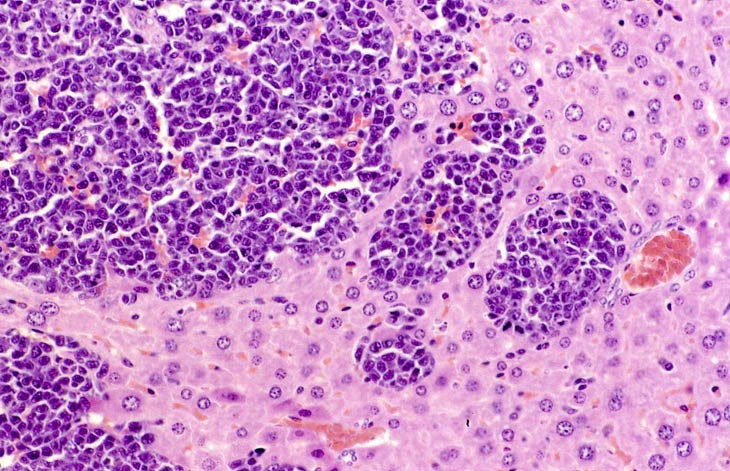

Erythroleukemia is a spontaneous hematopoietic neoplasm of Tg.AC mice characterized by marked hepatomegaly. The affected liver is infiltrated by metarubricytes and less differentiated erythroid precursors.

A higher magnification of hepatic erythroleukemia.